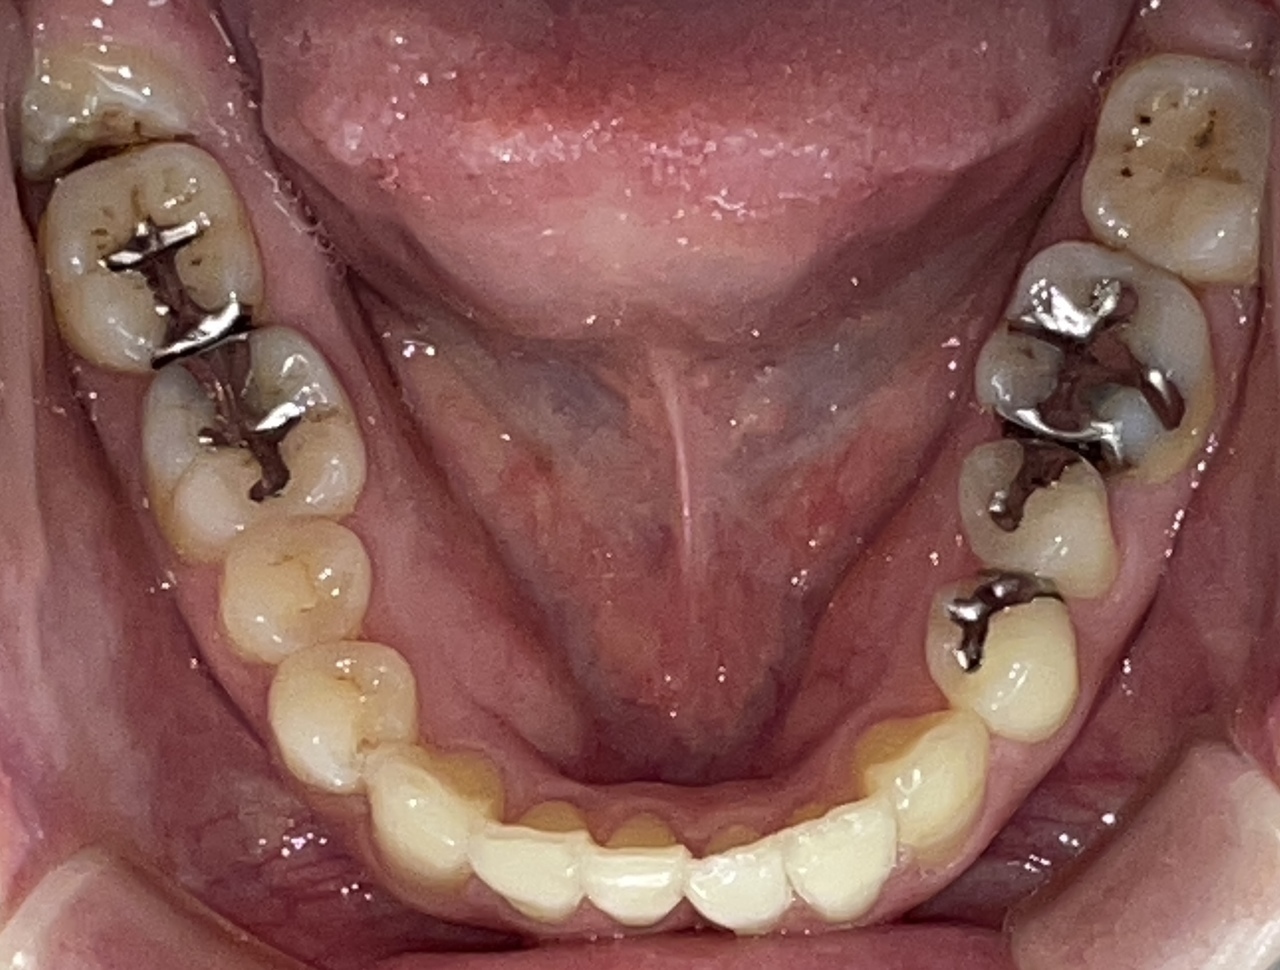

Before

After

矯正の種類 / invisalign GO

年齢・性別 / 40代男性

主訴  /  叢生

治療期間 / 17ヶ月

費用 / 簡易検査 5,000円(税別) 精密検査 30,000円(税別)

両顎マウスピース 450,000円(税別) 両顎リテイナー料 60,000円(税別)

※マウスピース交換時別途調節料5,000円(税別)

副作用 / 口内炎・歯の移動に伴う痛み・知覚過敏 ※数日で収まる場合が多いです

リスク / 後戻り防止の為、夜のみマウスピースで保定を指示